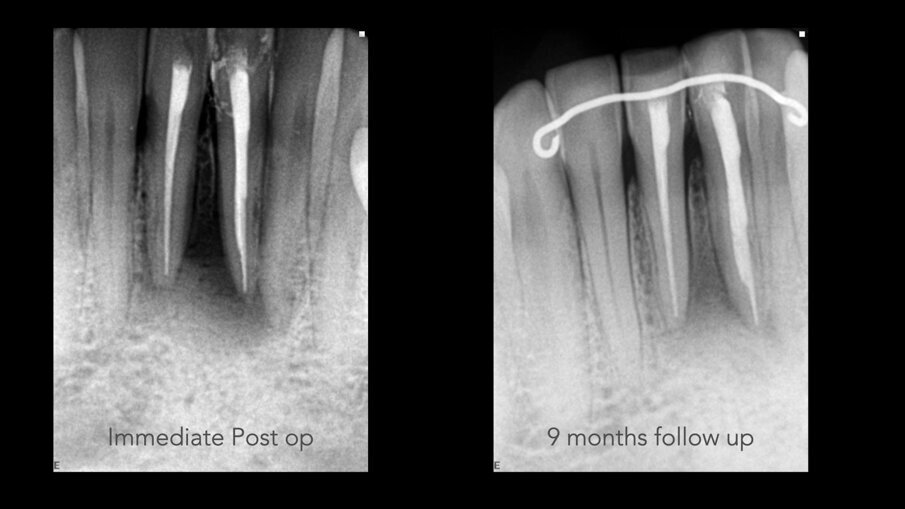

Slike 4a i b: Rendgenski snimci koji pokazuju neposrednu postoperativnu situaciju (a) i situaciju nakon devetomesečnog praćenja (b)

Nedelju dana posle operacije, šavovi su uklonjeni i postavljen je finalni ispuni u obe pristupne šupljine centralnih sekutića. Urađena je radiografija neposredno nakon operacije, kao i snimak nakon devet meseci od intervencije. Poređenje snimaka pokazalo je apoziciju kosti između dva centralna sekutića (slika 4). I-CAT skeniranje je takođe napravljeno u devetomesečnom period praćenja kako bi se proverio rast kostiju. Horizontalni pogled, uzet na istom nivou kao i preoperativno, jasno je pokazao smanjenje zazora sa 14,11 mm na 4,42 mm. Isti trend u lečenju (slika 5) pokazao je vertikalni pogled -kost na bukalnoj ploči je rasla prema korenu vertikalno (slika 6) skoro 8,2 mm visine tako da je kost bila vraćena i u direktnom je kontaktu sa korenovima zuba. Zaista, kada se obezbedi „skela“ na kojoj može da raste, kost može rasti u svim pravcima, uključujući i vertikalno, gde je postojao otvoreni parodontalni džep.